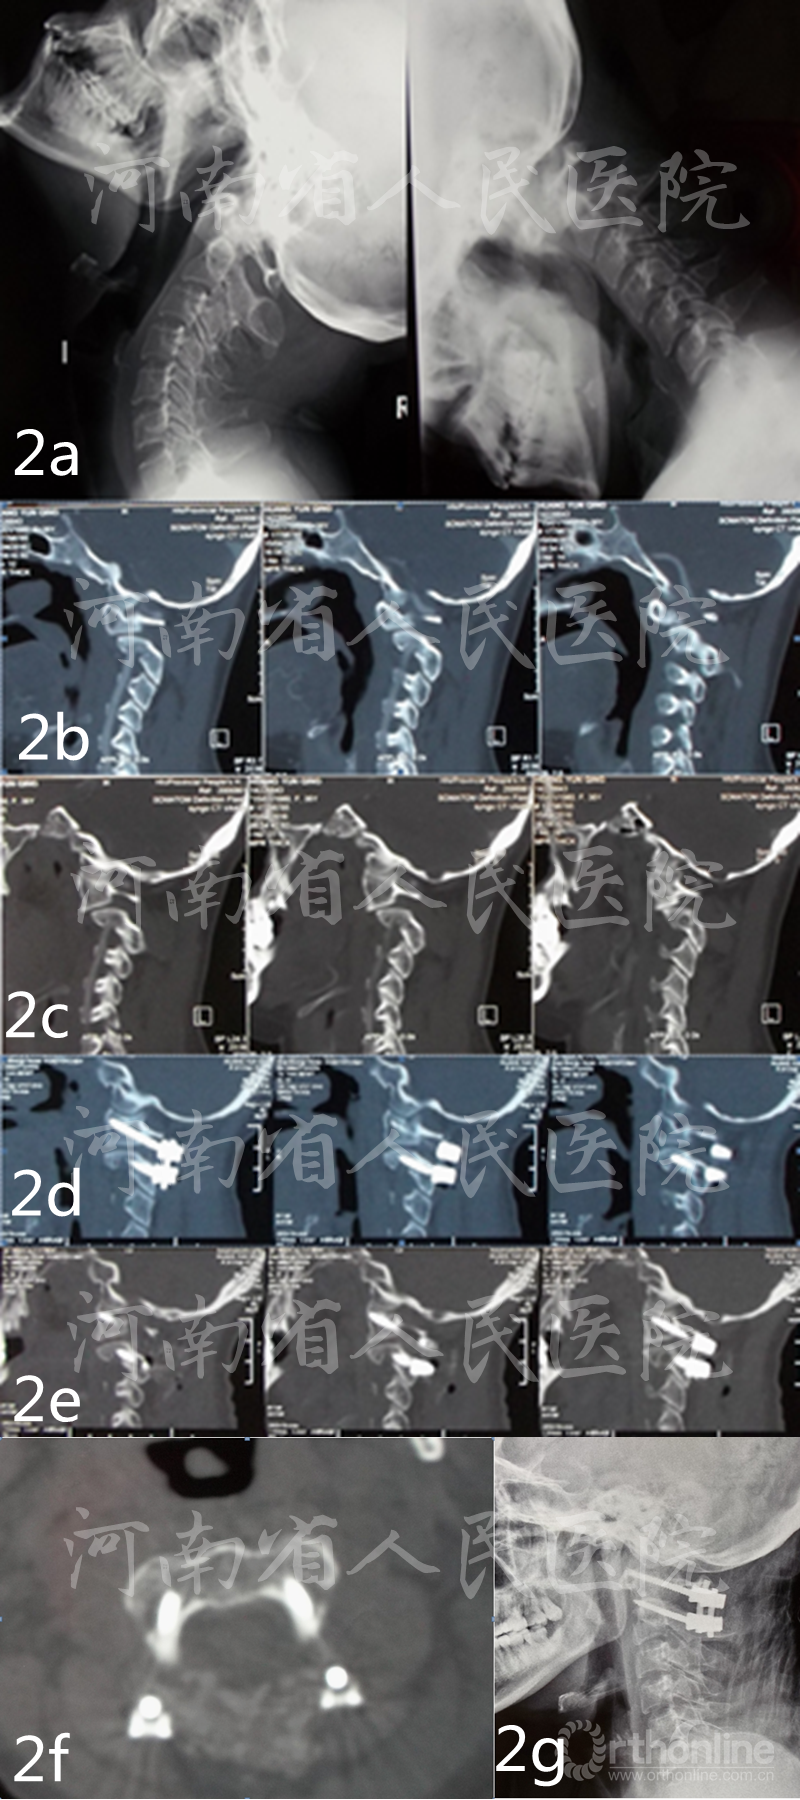

图2 患者女性,36岁,类风湿性关节炎,寰枢椎不稳 a术前X显示寰枢椎过伸位复位,过屈位脱位 b术前矢状位CT示枢椎右侧椎弓根发育不良c术前矢状位CT示枢椎左侧椎弓根发育不良d术后矢状位CT示枢椎右侧椎弓根钉为“in-out-in”三皮质螺钉e 术后矢状位CT示枢椎左侧椎弓根钉为“in-out-in”三皮质螺钉f术后轴位CT示双侧枢椎椎弓根螺钉为“in-out-in”三皮质螺钉 g术后6月X线示内固定位置良好,复位无丢失

患者均获得随访8-20个月,平均12个月,术后6个月影像学检查见植骨融合,无内固定松动,断裂发生。术后7d及末次随访VAS评分分别为(1.13±0.72)分,(1.07±0.81)分,较术前明显减轻;术后7d及末次随访时JOA评分分别为(12.9±1.8)分,(13.8±2.1)分,与术前比较明显改善。(表1)(图1、2)